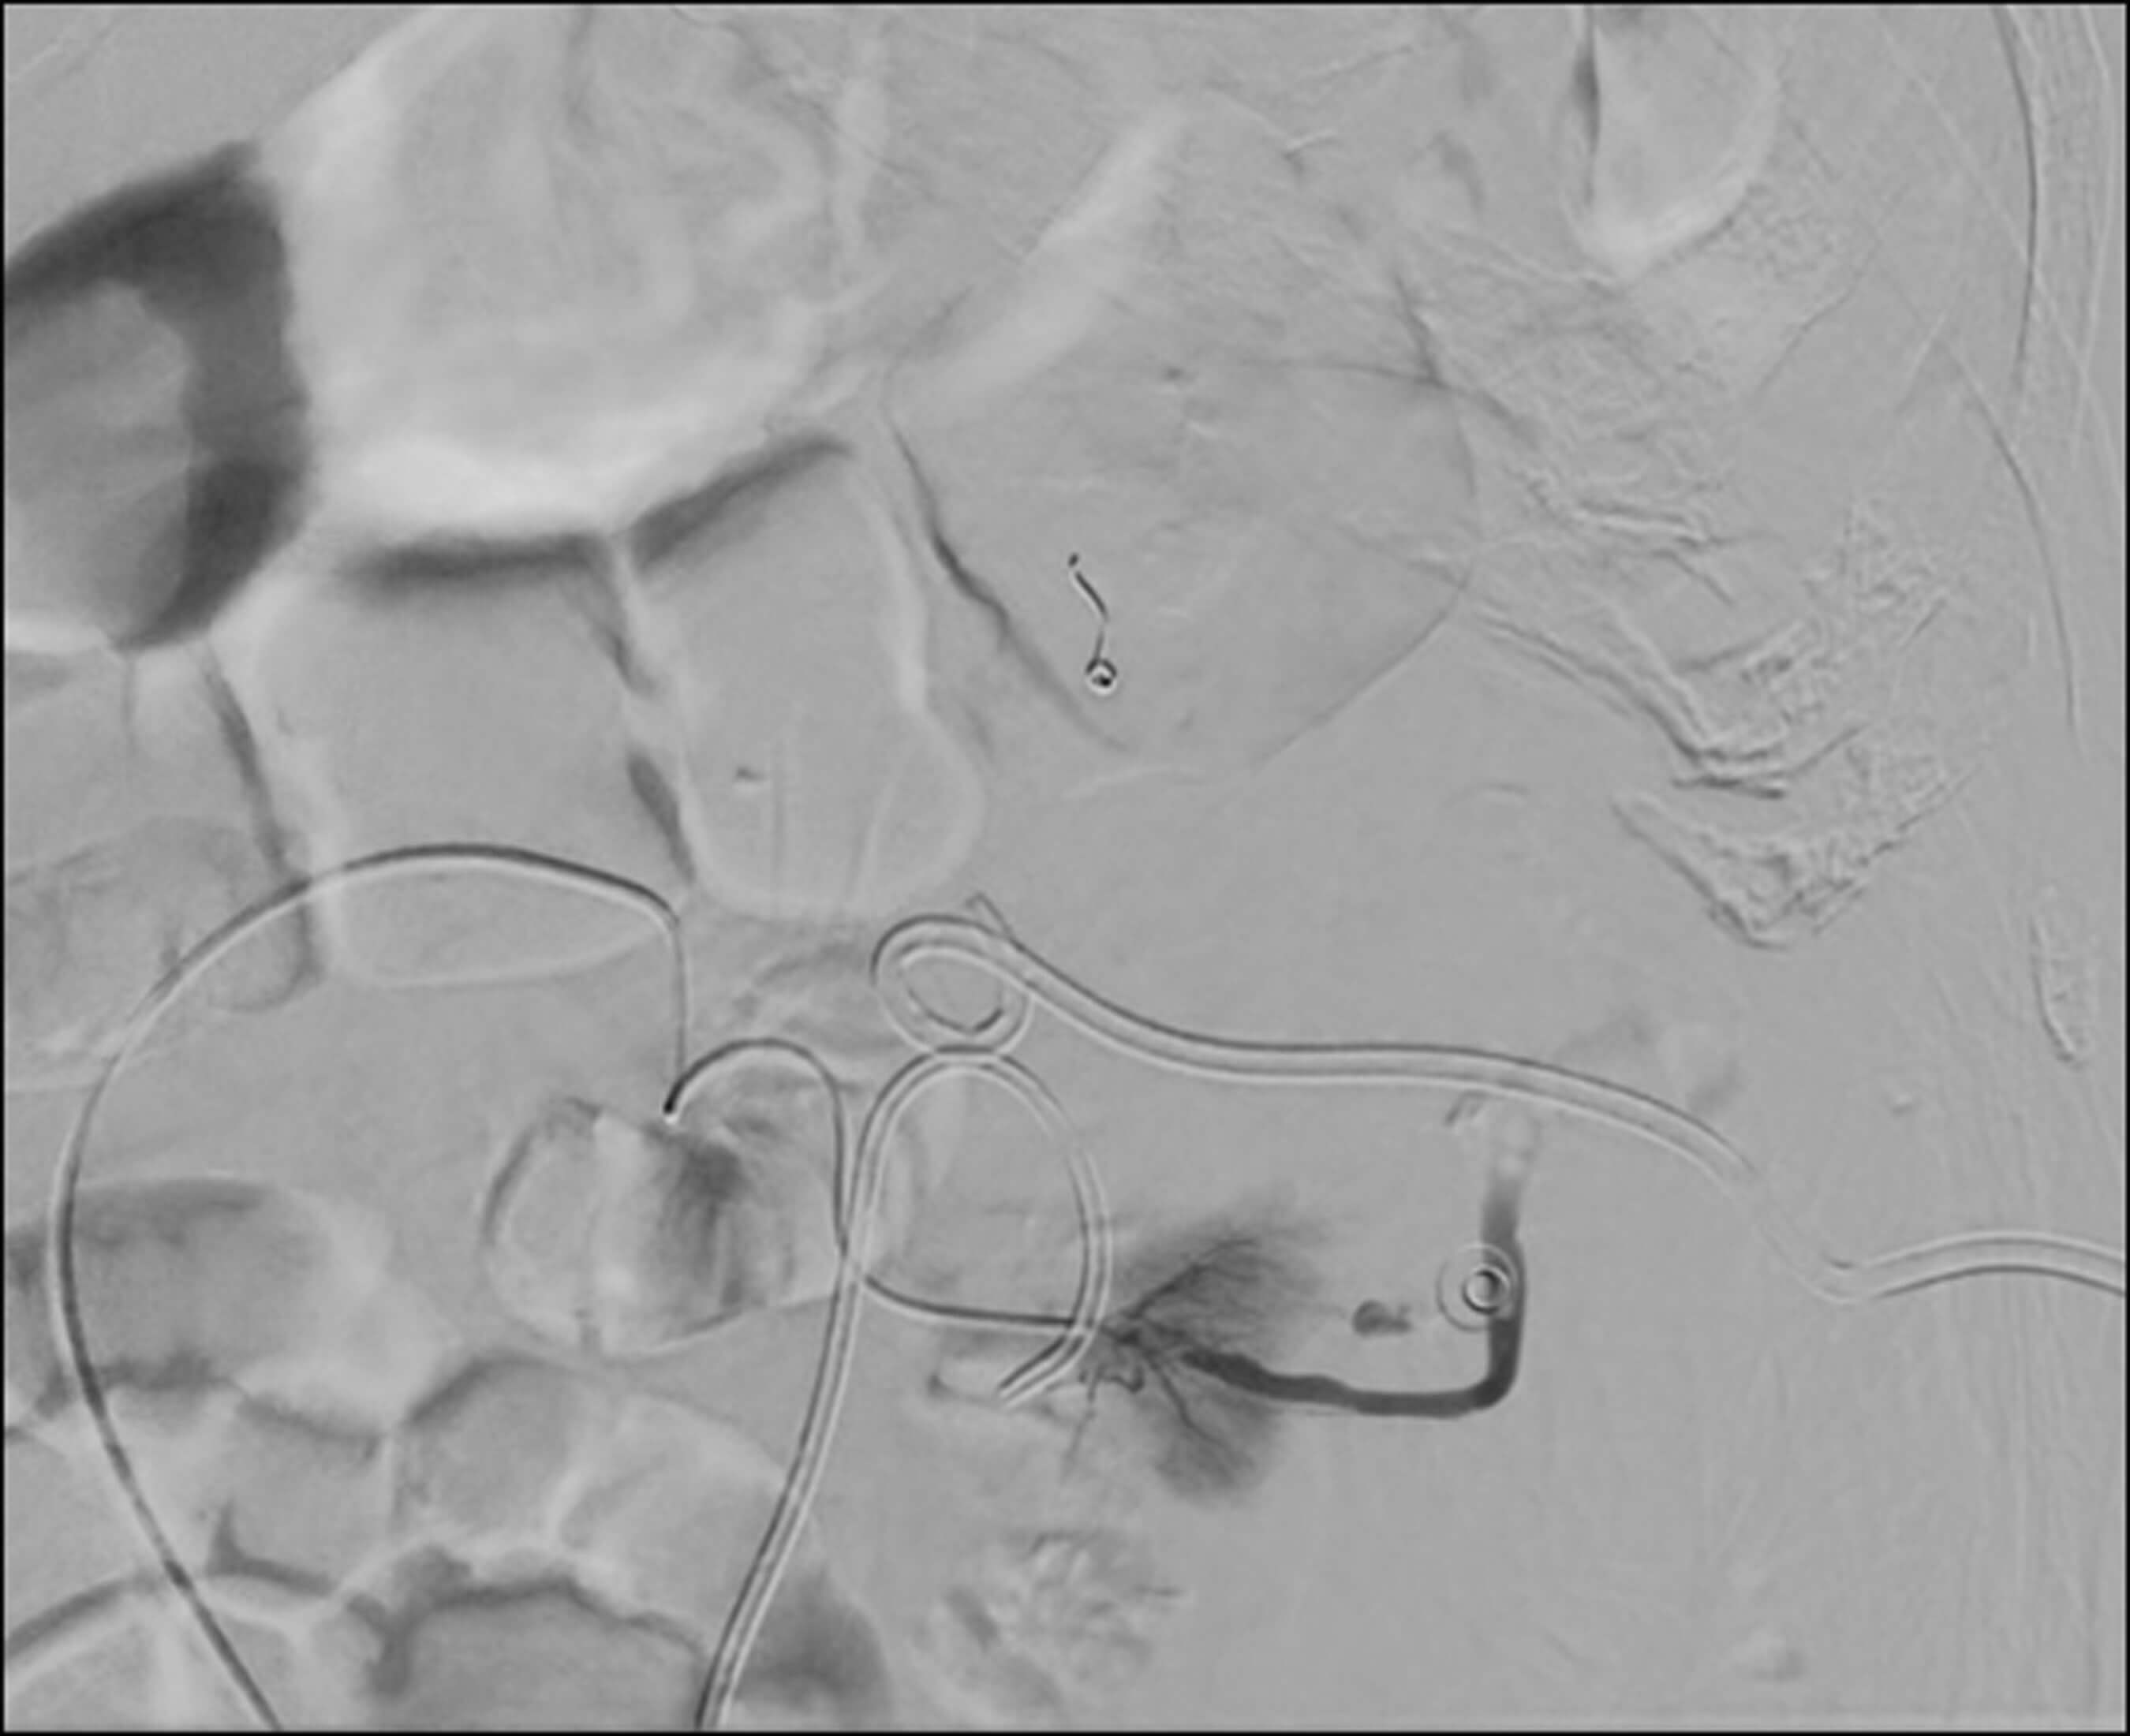

A 74-year-old male patient presented with visible haematuria and clot retention with a background of radical prostatectomy and salvage radiotherapy for a Gleason 9, T3b N1 M0 prostate cancer 13 years ago. The patient was managed for haemorrhagic radiation cystitis and was taken to theatre for bladder washes and diathermy twice but this had very little effect. Embolisation of bilateral superior vesical arteries was performed by interventional radiology (Figure 2). Post procedure, the patient recovered well and his haematuria settled prior to discharge.

Figure 2.